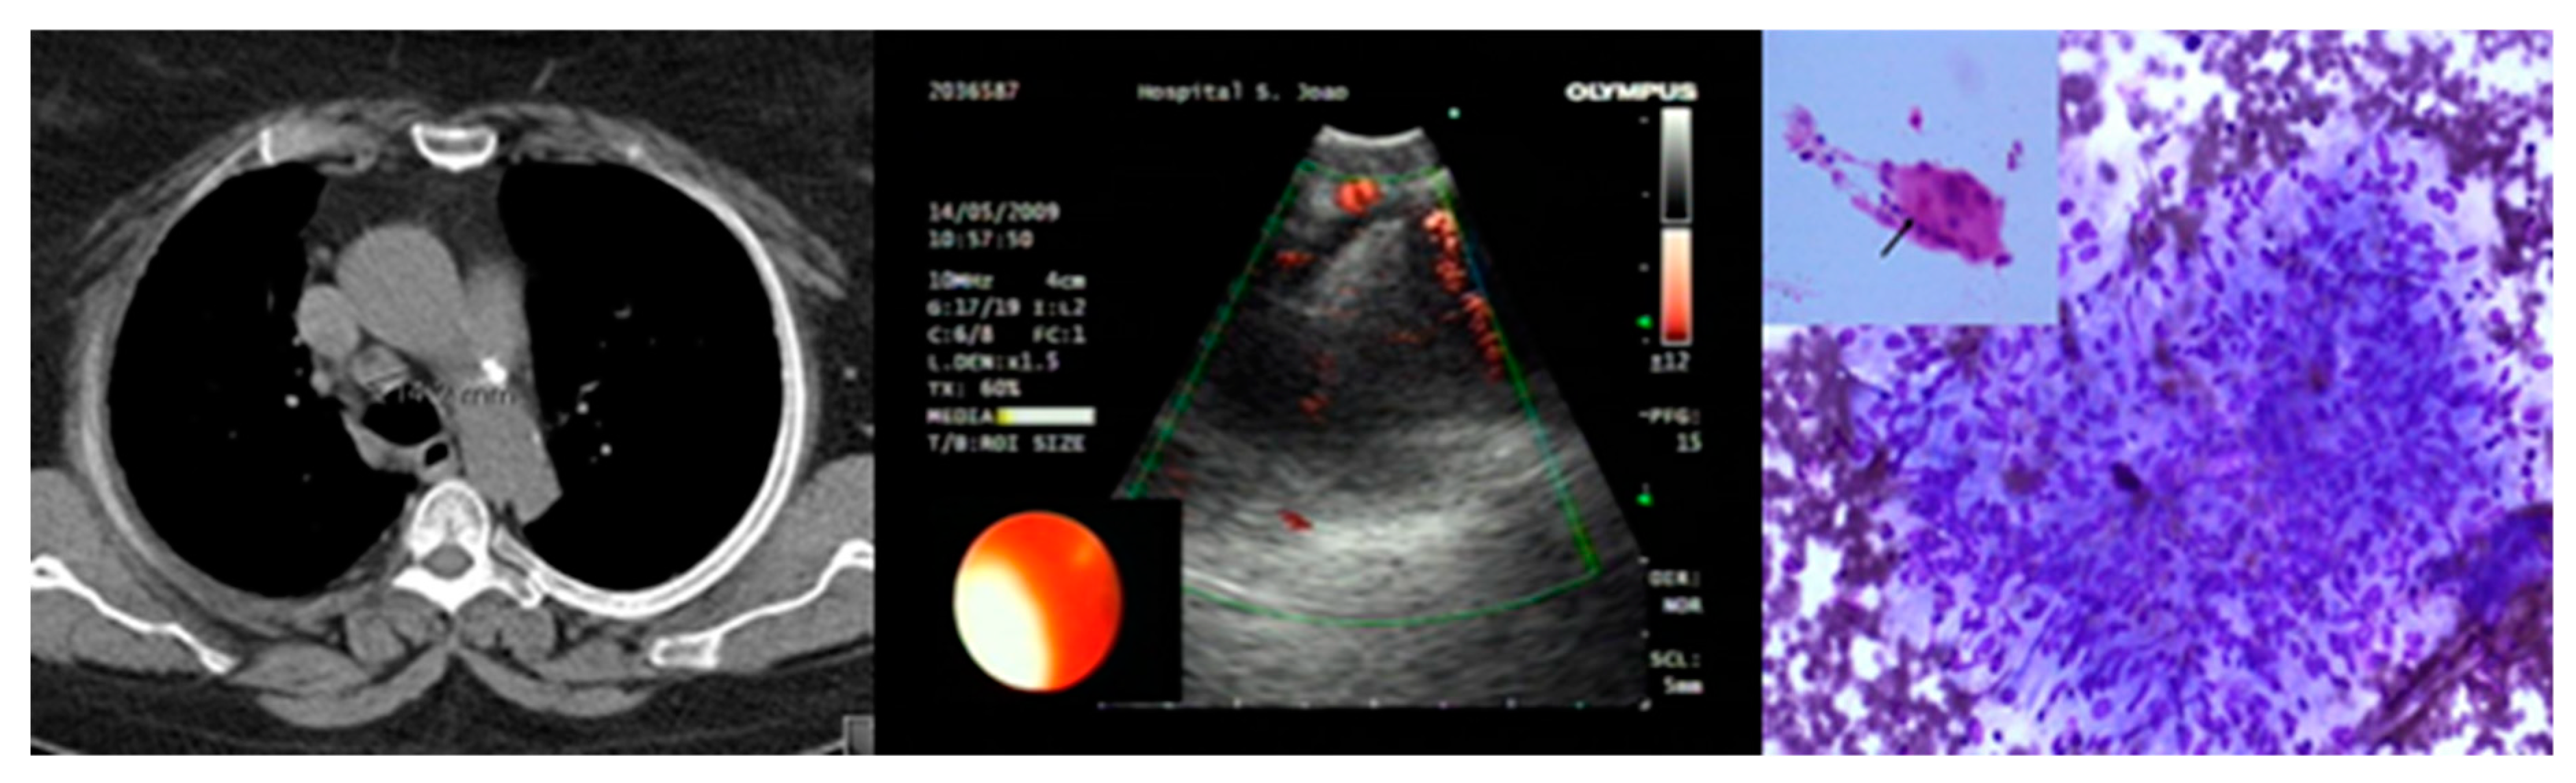

3.1. Endobronchial Ultrasound-Guided Transbronchial Needle Aspiration (EBUS-TBNA)

3.2. Endoscopic Ultrasound-Guided Fine Needle Aspiration (EUS-FNA)